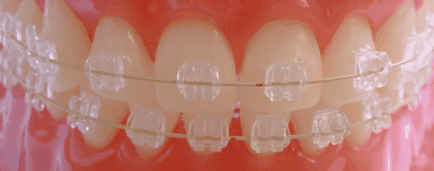

Снимка: сложно при лошо захапка, която изисква продължително лечение

В тази група фактори са тези, които са напълно уникални за всеки отделен случай. Въпреки това, тяхното разбиране за необходимостта да се говори накратко за колко трудно може да бъде преместен пред които са изправени зъби.

Двата края на челюстта алвеоларни процес като алвеолите на (отвори), които са разположени и скрити части на зъба. В тези ямки самата зъба се провежда поради периодонталните тъкани около него.

Влакната на тези тъкани проникват в двете страни в същото време - в цимента на корена и алвеолите, ги свързва в единна система. Това е така, защото на този слой на зъбите и да има относителна подвижност.

В допълнение, под постоянно излагане може да варира и челюстта. Тя започва да се разтваря в частта, където зъба се премества под влияние на постоянно налягане, генерирана от скоби.

Но обратната страна, на костната тъкан се пресова и расте. Всичко това се дължи на компресията или разтягане на пародонтални след това на мястото са започва да се променя в големи количества, за да се образува остеокластите и остеобласти.

Тези клетки допринасят съответно резорбция или образуване на кости.